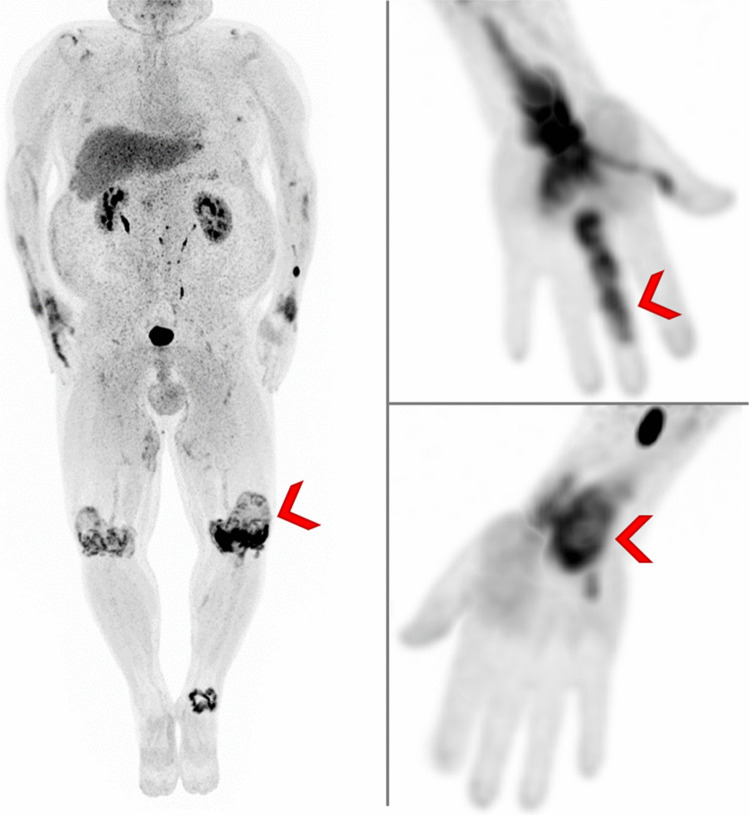

Imaging molecular processes associated with inflammatory disease has been revolutionized by hybrid imaging using positron emission tomography/computed tomography (PET/CT). PET/CT visualizes metabolic activity as well as protein expression and provides a comprehensive whole-body evaluation. It has the potential to reveal inflammation prior to detection of structural changes in inflammatory joint diseases. FAP is a type II transmembrane glycoprotein overexpressed not only in the stroma of tumors but also in the fibrotic processes of certain immune-mediated disorders. The recent introduction of fibroblast activation protein inhibitors (FAPI) labeled by positron emitters and thus suitable for PET/CT allows to investigate FAP expression in vivo. This review will focus on the use of FAPI-PET/CT for the diagnosis and evaluation of treatment response in inflammatory joint diseases.